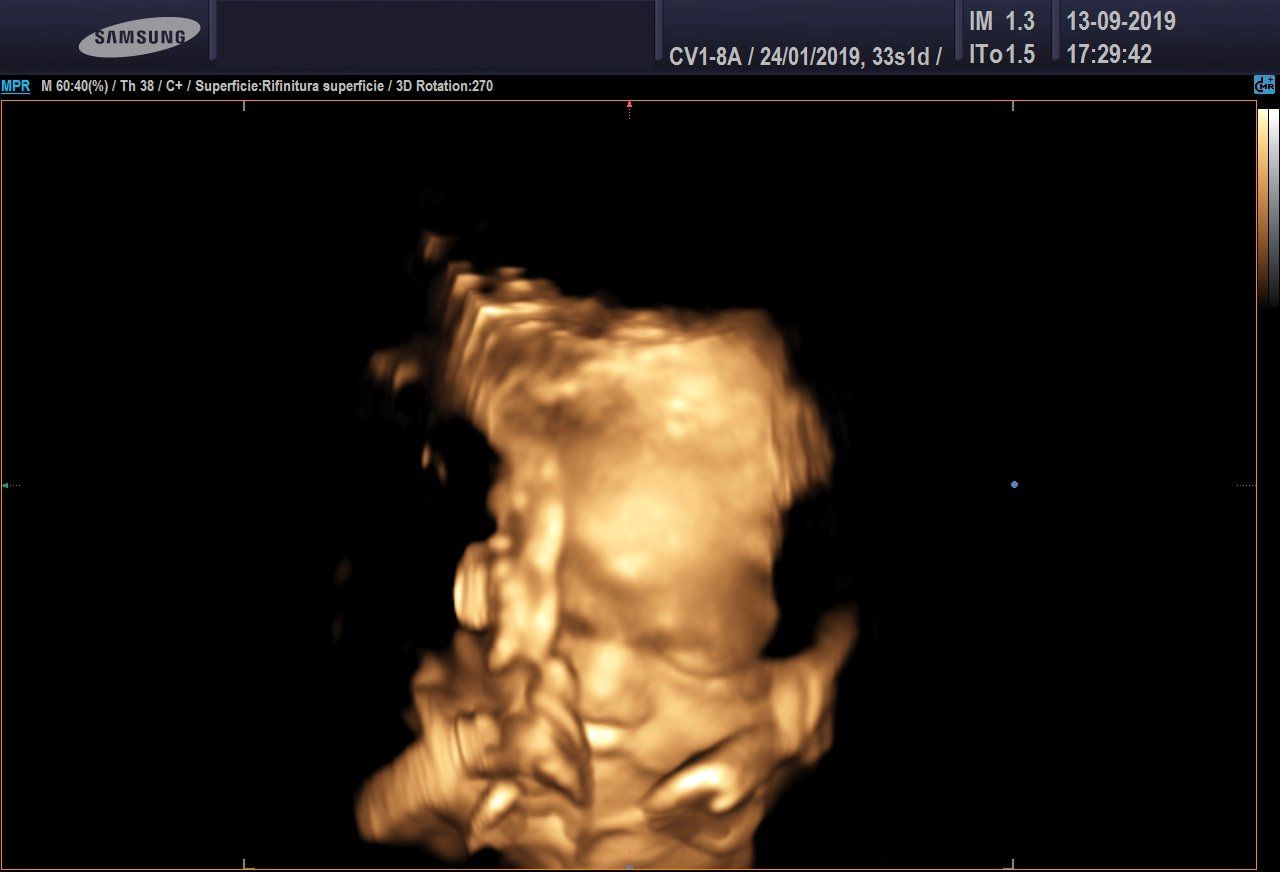

Ecografia 3D/4D

L'ecografia 3D consente di ottenere delle immagini statiche, non in movimento, ma in pratica delle foto delle fattezze del feto.